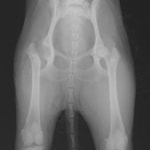

症例1 ゴールデン・レトリバー 7歳 避妊雌

後肢の跛行を主訴に来院されました。レントゲン検査にて、左右股関節の形成不全および重度の関節炎所見を認めました。THRに関しては適応年齢(約9カ月齢以降)の範囲にありますが、左右とも長期に及ぶ骨関節炎の進行により、大腿骨頭・寛骨臼ともに重度の骨変形を伴っていました。このような症例において、THRのカップの定着が悪くTHRの手術の成功率が下がるため、機能回復の面では劣りますが、症状がより重いと判断された左後肢の大腿骨頭・骨頚切除術を実施しました。今後は、リハビリテーションを行い、患肢の機能回復に努めると共に、反対側の大腿骨頭・骨頚切除術を検討していく予定です。

術前レントゲン